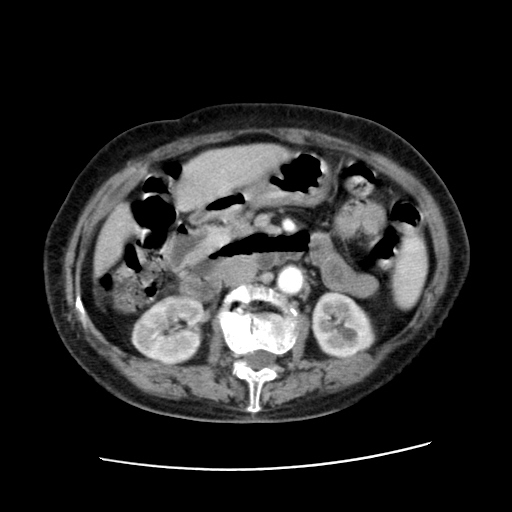

标题: CT25203:上腹部增强,看看

女,77.无不适

肝脏变异、异位胆囊,肝右叶肝内胆管结石并肝内胆管扩张。

肝右叶肝内胆管结石并肝内胆管扩张。胆总管下段梗阻,考虑壶腹部占位。

肝右叶肝内胆管结石并肝内胆管扩张。胆总管下段梗阻,考虑壶腹部占位。支持